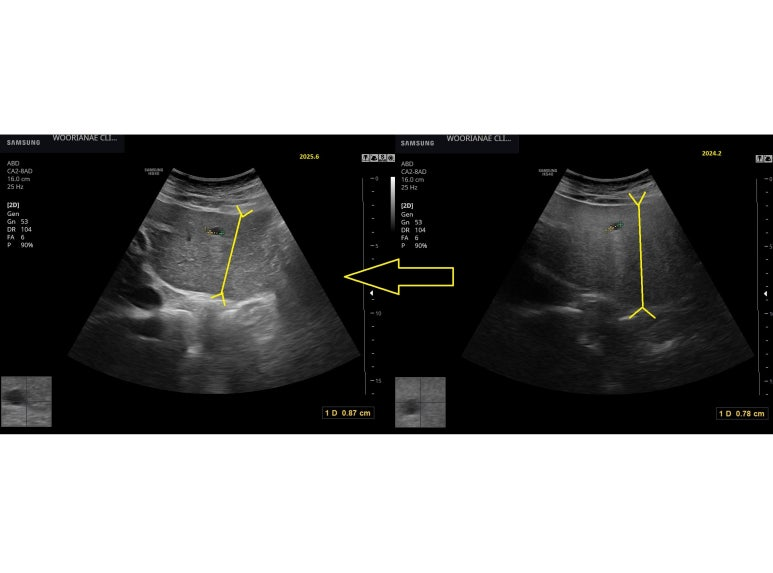

정기 간암평가 초음파 시행

왼쪽 간 표면에 뚜렷한 물결모양의 표면

특이 S2/3 경계와 S4 본휙에서 표면의 굴곡이 뚜렷/심하다.

1년전 사진과 비교하면 그때는 뚜렷하지 않아 보이며, 지방간으로 음영의 증가 차이도 뚜렷하다.

음영뿐만 아니라 지방간에 의한 효과로서 간의 부피의 차이도 정성적으로 느껴진다.

rGTP만의 추세로 보면 초진 이후 음주를 더 줄였다가 24.2월경에는 좀더 마신것으로 (초진때 만큼은 아니라고해도) 보인다. 이후 rGTP는 상대적으로 감소하였고... 초음파에서 지방간 변화도 느낄수 있다.

; 지방간에 의한 비대 효과가 적어지니 표면의 굴곡이 더 두드러져 보이는 것으로 보인다. 간경화로 기술하면 되겠다.